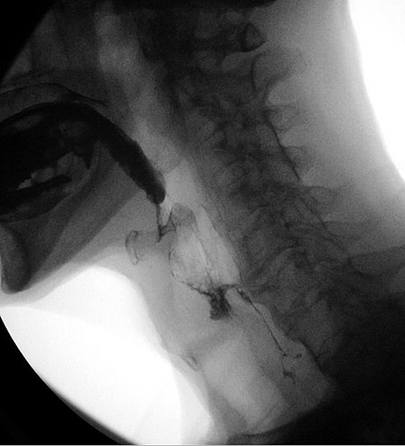

Estudio videofluoroscópico de la deglución - Videofluoroscopic swallow study (VFSS).

Un estudio videofluoroscópico de deglución (VFSS), también conocido como examen de deglución de bario modificado, es un examen dinámico de rayos X de la cavidad oral, la faringe y el esófago cervical. El VFSS permite evaluar la función de deglución del paciente mediante la administración de líquidos y sólidos de distinta consistencia para evaluar la deglución fluoroscópicamente.